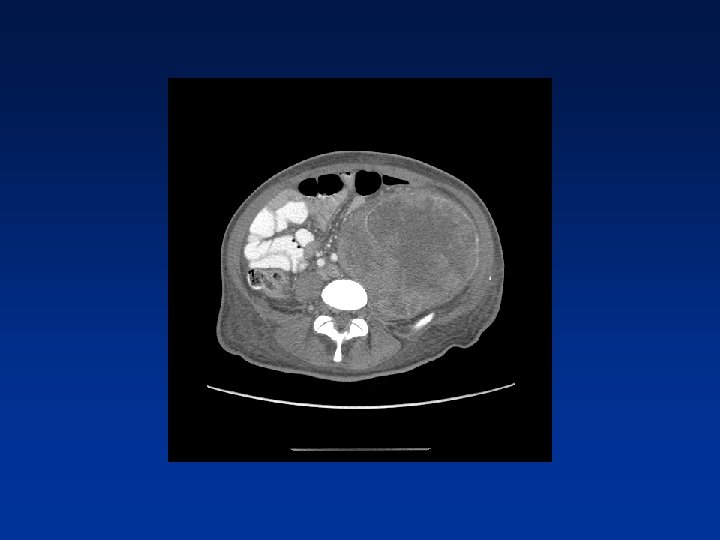

CASE